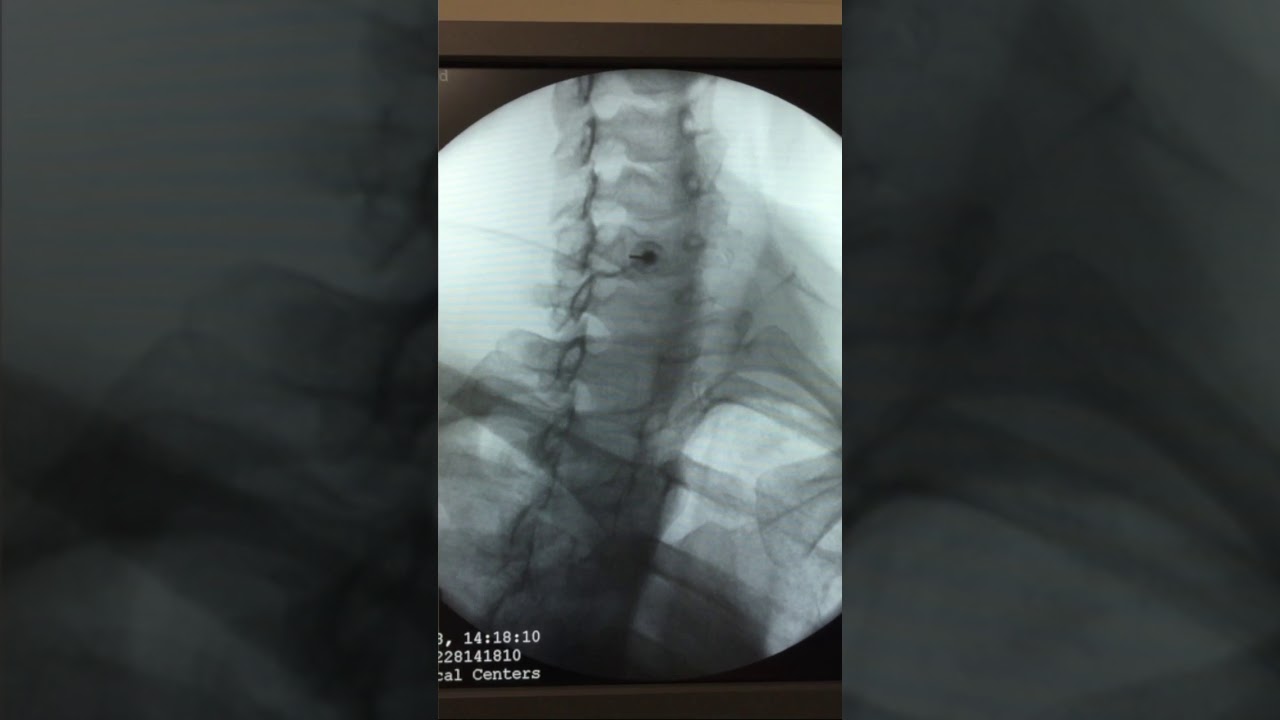

The procedure is guided using x-ray photography. First, Dr. Hatgis locates the target level of the cervical spine via x-ray. A contrast material is injected at that level, which allows him to see the SGB medication as it is administered. 👀 As the SGB medication is administered, the x-ray imaging allows Dr. Hatgis to make sure that the medication spreads correctly. -